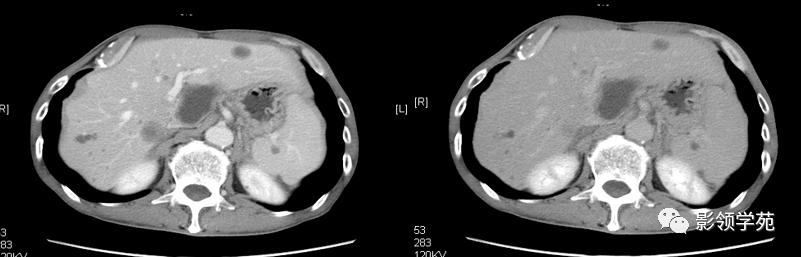

脾脏正常ct及常见疾病影像表现

脾脏疾病的ct诊断